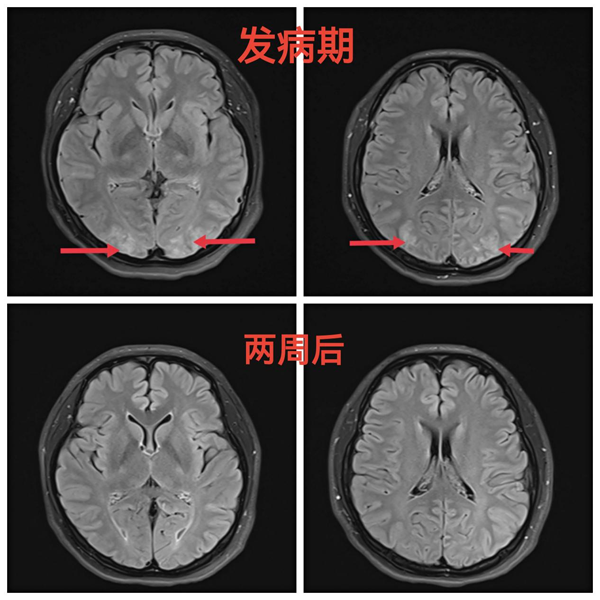

双胎宝妈产后头痛 神经内科手到病除

双胎宝妈产后头痛 神经内科手到病除 2021年08月12日是27岁的患者王女士最开心幸福的日子,这一天她于我院产科顺利生下双胞胎儿子,一家人都沉浸在新生命诞生的…